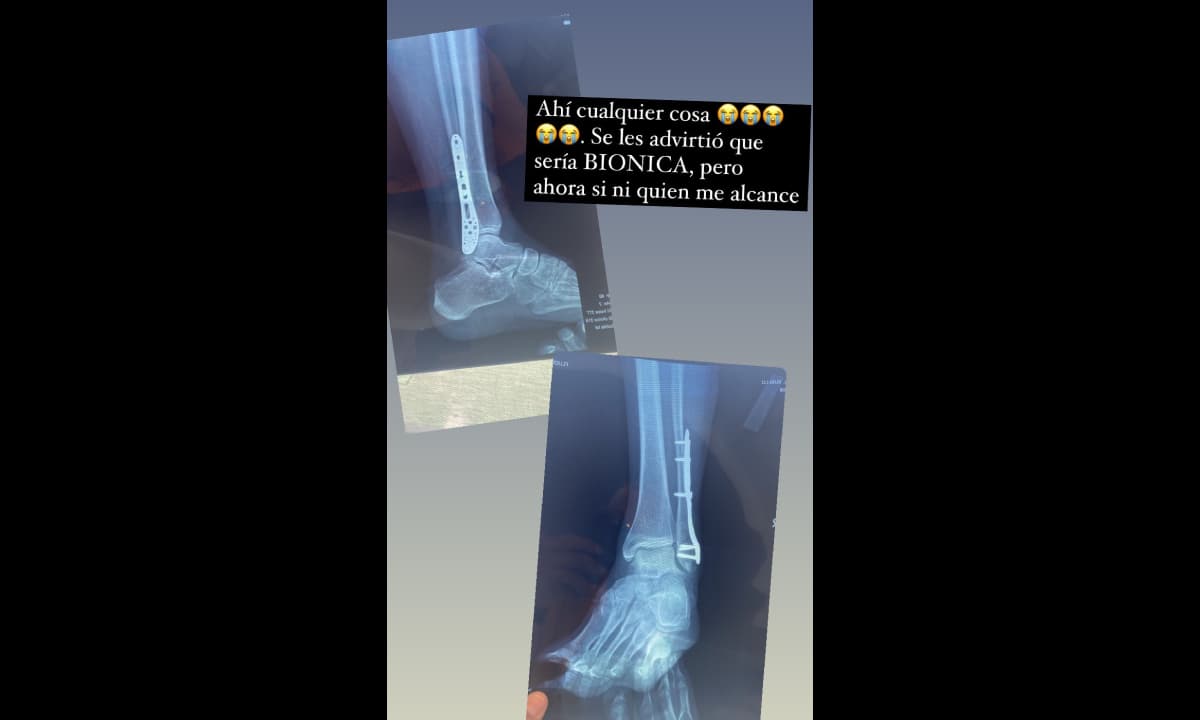

La actriz, quien tiene tres hijos con el presentador, expresó que la sometieron a una cirugía del pie derecho; aunque no dio más detalles sobre qué fue lo que pasó, sí bromeó al respecto, asegurando que a raíz de la intervención sería biónica e incluso mostró que le colocaron una pieza en la extremidad.

“Y de regreso, dónde quedó el glamour y listo, gracias a Dios todo salió bien. Ahora ánimo para la rehabilitación. Ahí cualquier cosa. Se les advirtió que sería biónica, pero ahora sí ni quien me alcance”, señaló Susy Lu como descripción de sus últimas publicaciones, en las que mostró el resultado de la operación que vivió.